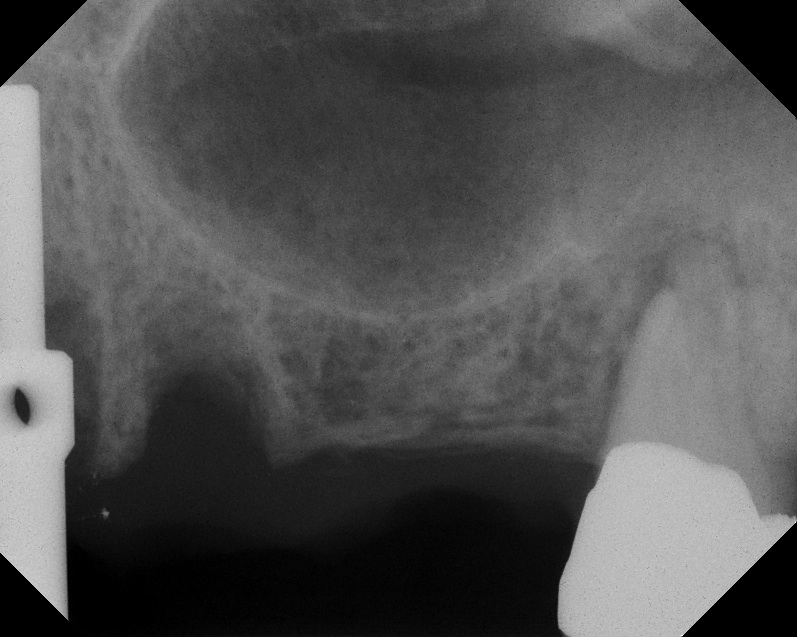

Case 1. Preoperative radiograph showing a ridge height of about 2 mm to 3 mm in the No. 14 position.

Fig. 13

A 74-year-old man presented with only about 2 mm to 3 mm of native bone below the sinus in the No. 14 position (Figure 13). The composite graft used was an approximately 50:50 mixture of DFDBA (Bio-Oss®, Geistlich Biomaterials, www.bio-oss.com) with the addition of about 40% calcium sulfate by volume (Figure 14). The implant placed (Figure 15) was a 10-mm long, rough-surfaced, platform-shifting implant (tapered 4.2 mm to 2.8 mm), and the sinus was raised about 8 mm. The postoperative radiograph taken at 4 months (Figure 16) showed some shrinkage of the graft, but no demarcation of the old sinus floor in the area.